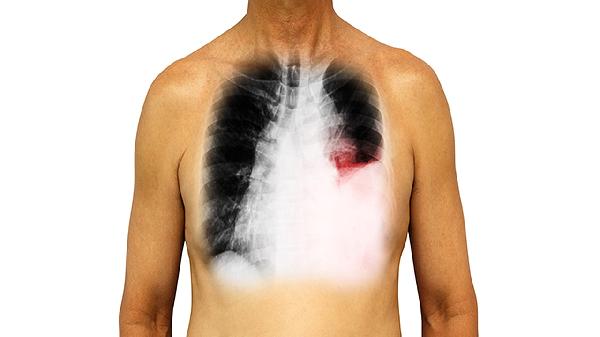

运动时呼吸困难呈进行性加重,初期仅在爬楼或快走时出现,后期静息状态下也会发生。这与肺泡-毛细血管单位受损导致氧气弥散障碍直接相关。

约50%患者出现手指末端膨大呈鼓槌状,因长期慢性缺氧导致软组织增生。该体征在特发性肺纤维化患者中尤为显著,可作为疾病进展的参考指标。